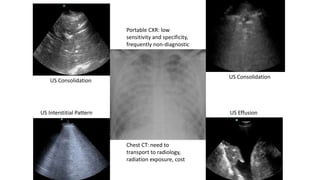

Portable CXR: low

sensitivity and specificity,

frequently non-diagnostic

Chest CT: need to

transport to radiology,

radiation exposure, cost

US Consolidation

US Effusion

US Interstitial Pattern

Portable CXR: low sensitivityand specificity, frequently non-diagnostic Chest CT: need to transport to radiology, radiation exposure, cost US Consolidation US Effusion US Consolidation US Interstitial Pattern